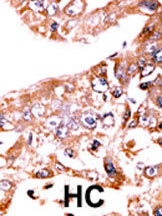

Formalin-fixed and paraffin-embedded human cancer tissue reacted with the primary antibody, which was peroxidase-conjugated to the secondary antibody, followed by AEC staining. This data demonstrates the use of this antibody for immunohistochemistry; clinical relevance has not been evaluated. BC = breast carcinoma; HC = hepatocarcinoma. |